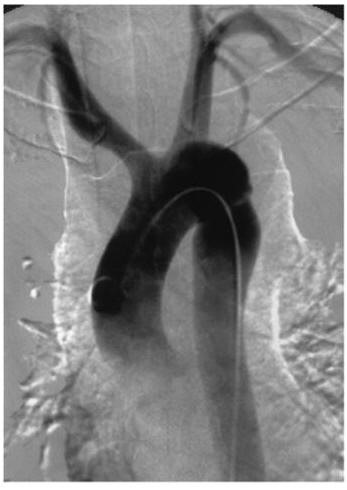

Аортография — это методика рентгенологического исследования аорты, основанная на получении комплексного изображения аорты вследствие заполнения её контрастным веществом. Главным инструментом в данном случае выступает радиоактивное излучение, с помощью которого производятся снимки наполненных рентгенконтрастной жидкостью сосудов.

При сохранении пульсации артерии в бедренной части прокол осуществляется именно там (методика Сельдингера). В полученный прокол вставляется тонкий струнообразный проводник, посредством которого в дальнейшем вводится катетер. Проводник извлекается, а катетер проводится непосредственно в аорту. После этого производится введение рентгенконтрастного препарата. Далее с помощью рентгеновского аппарата выполняется ряд снимков исследуемой области, после чего катетер удаляется, а на место прокола накладывают асептическую давящую повязку для предотвращения кровотечения. Полученные снимки хранятся на жёстком диске компьютера, что позволяет врачу обращаться к ним в любой момент.